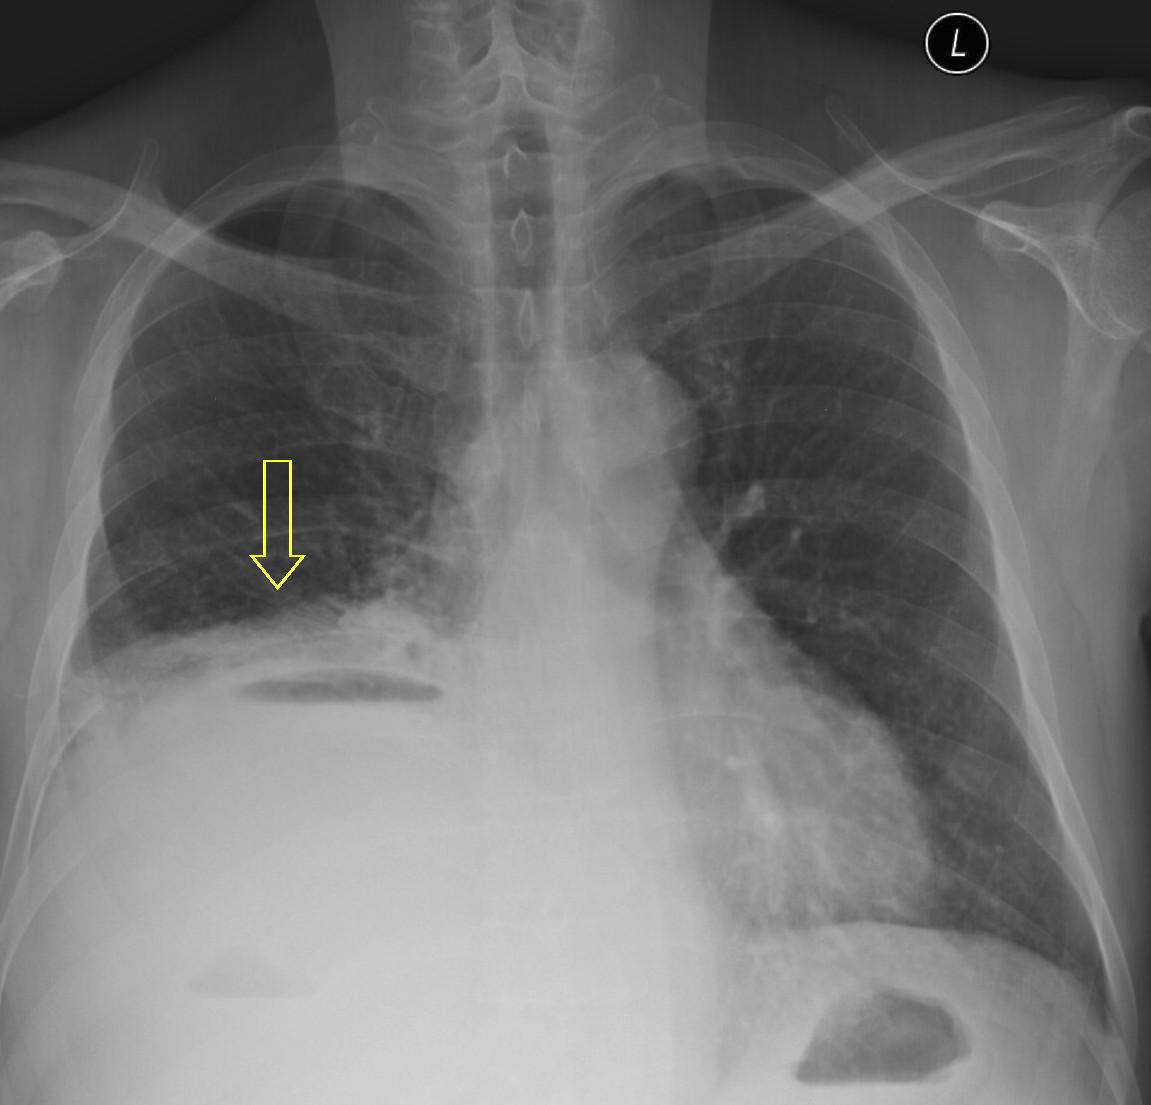

Image

6. c

6. d

64 year old man. Infiltration and abscess development in the right lower lobe.

c.) CT lung window, coronal reformat, d.) axial, mediastinal window. Extensive area in the right 8-9th segments without air, including many associated lesions of fluid density, with tiny air bubbles, larger air spaces and air-fluid level. The lesion has almost a triangular shape, its dorsal and ventral contours are arched, its peak points towards the lower pole of the hilum.